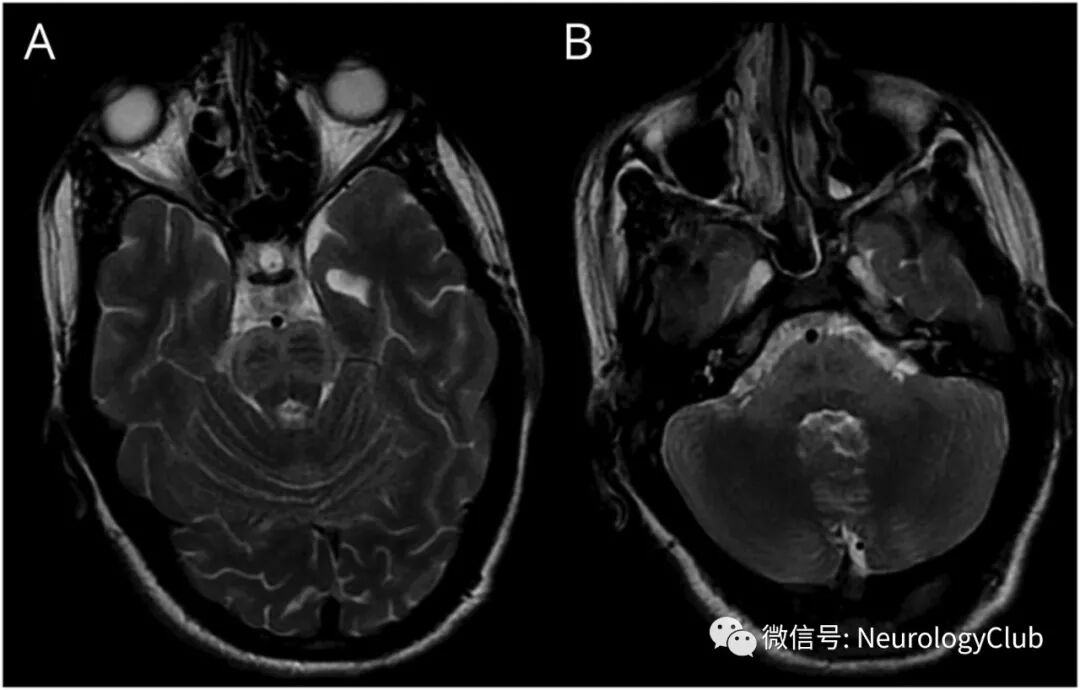

16岁男孩,4岁时罹患麻疹,出现全面性肌阵挛性抽搐和进行性认知和感觉功能下降6月余。脑电图可见全面性,周期性,高幅放电(图1)。头颅MRI可见腹侧脑桥和小脑中脚孤立性T2高信号(图2)。

(图2:脑MRI可见腹侧脑桥[A,B]和双侧小脑中脚[B]T2WI高信号)